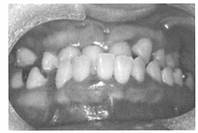

(1)歯科的特徴

@歯の特徴

歯の先天欠如、倭小歯(永久歯)、 円錐歯(上顎側切歯)、短根歯、上顎側切歯先天欠損。

A顎骨の特徴

上顎劣成長による狭口蓋、反対咬合と交叉咬合、空隙歯列や叢生が多い。

B軟組織の特徴

大舌、舌突出、溝状舌、

筋緊張低下による開口、および口唇の乾燥がみられます。